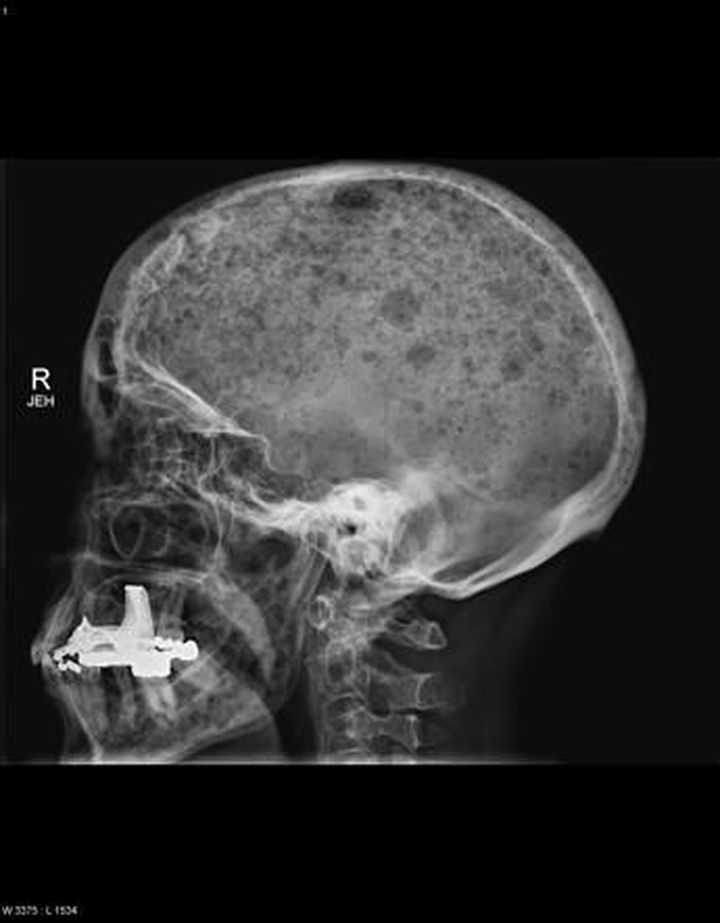

The raindrop skull is a typical striking feature of multiple myeloma. Innumerable well circumscribed 'punched out' lytic lesions can be best seen in the lateral view of the skull. An easily learnt mneumonic for the symptoms of multiple myeloma is "CRAB" 🦀 🦀 🦀 C- calcium elevated R- renal failure A- anemia B- bone lesions (lytic) and bone pain 🦀 🦀 🦀